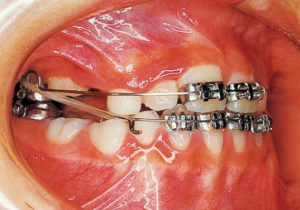

15 3-23-’91 Before surgery

16 5-9-’92 After Phase 2 Treatment

Pre-surgical orthodontic period: 9 months

Hospitalization period: 2 weeks

Intermaxillary fixation period: Approximately 1 month (orthodontic treatment was not possible during this period).